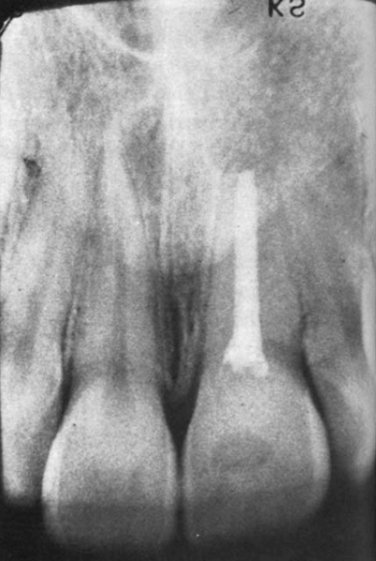

Пациент, девочка 14-лет впервые пришла на прием в 1966 году. Пульпа левого центрального резца верхней челюсти была травмирована в результате удара о дверь двумя неделями ранее (рис. 1). Эндодонтическое лечение было начато после осмотра в это же посещение и завершено через три недели (рис. 2).

Рисунок 1. — Клинический случай 1. Рентгенограмма левого центрального резца верхней челюсти, сделанная в 1966 году после травмы.

Рисунок 2. — Клинический случай 1 — Рентгенограмма после лечения.